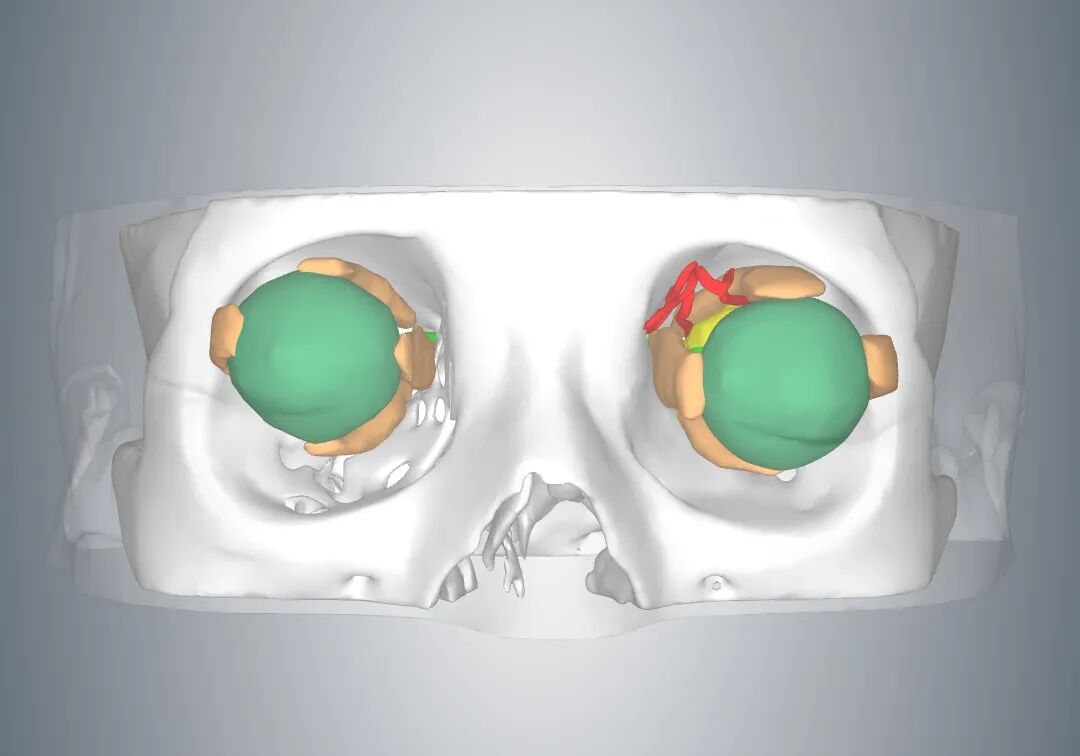

如何让手术创伤更小?宋艳向医学3D打印创新研究中心发出了会诊邀请。中心根据小王的眼部影像学数据,对肿瘤及其周边组织进行了可视化重建分析,为他建立起左眼的3D模型。

图片

3D模型

利用该模型,手术团队分析了肿瘤的位置,辨认出术中需要分离保护的血管、神经及重要组织,并且在术前进行了模拟手术规划。最终,手术团队从颞下穹隆结膜切口入路,历时30分钟,完整切除了肿瘤,周围神经血管都保护完好,切口仅1厘米,术后创伤小,患者恢复快。